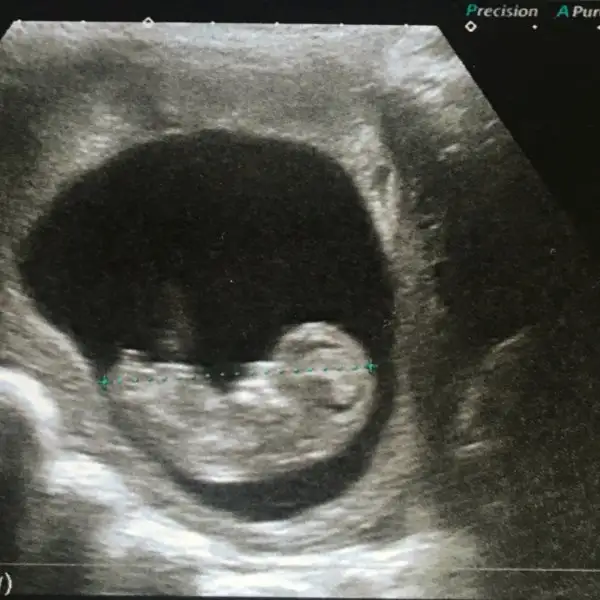

Maşallah kuzuyaŞurayada dünki ultrason görüntüsünü bırakıyorum.